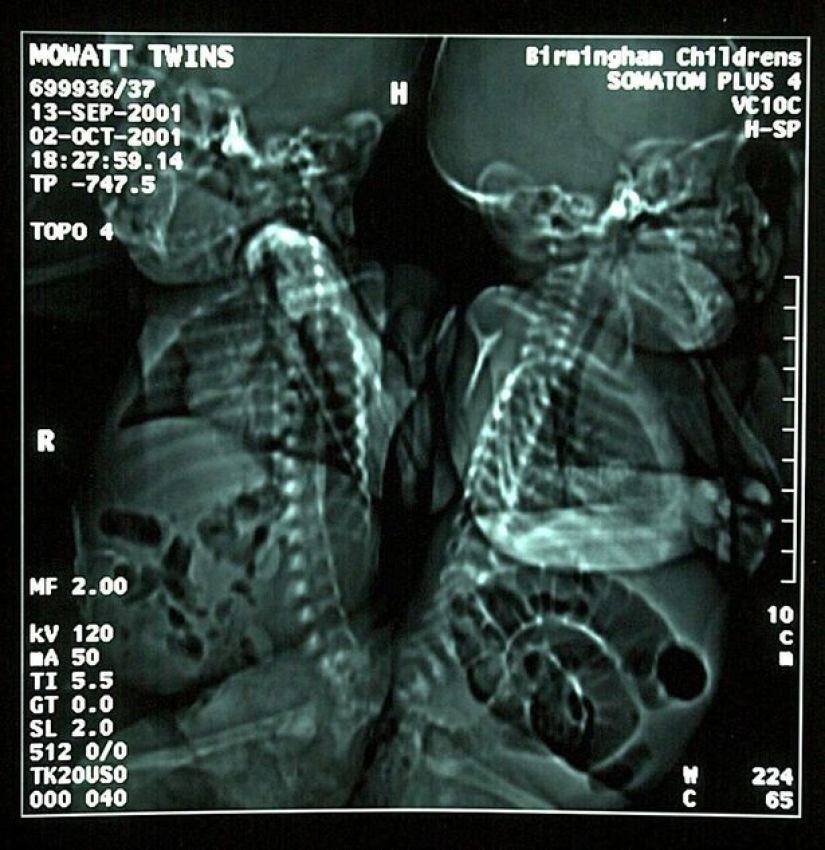

Eman y Sanchia Movatt nacieron el 13 de septiembre de 2013, cuatro meses antes de lo previsto, e incluso se fusionaron con spines. El hecho de que los médicos lograron salvarlos al nacer es un verdadero milagro. Otra cosa sucedió cuando las niñas tenían 3 meses de edad: los cirujanos lograron separar a los gemelos siameses, salvando sus vidas.

En el momento de la cirugía, los bebés pesaban juntos un poco más de 4 kg. La operación duró 16 horas y se convirtió en la segunda intervención quirúrgica exitosa en la historia de la medicina. Las posibilidades de supervivencia de las hermanas fueron estimadas por diferentes expertos del 5 al 25 por ciento, pero todo salió perfectamente.

A pesar de que una vez en 2001, los médicos crearon un milagro, no lograron preservar completamente las funciones de los gemelos separados. Cada una de las chicas tiene un defecto grave de la columna vertebral, y además, cada una de ellas tiene un lado desarrollado un poco peor y una pierna es más corta. Por lo tanto, los gemelos caminan con muletas, y Eman a veces usa una silla de ruedas.